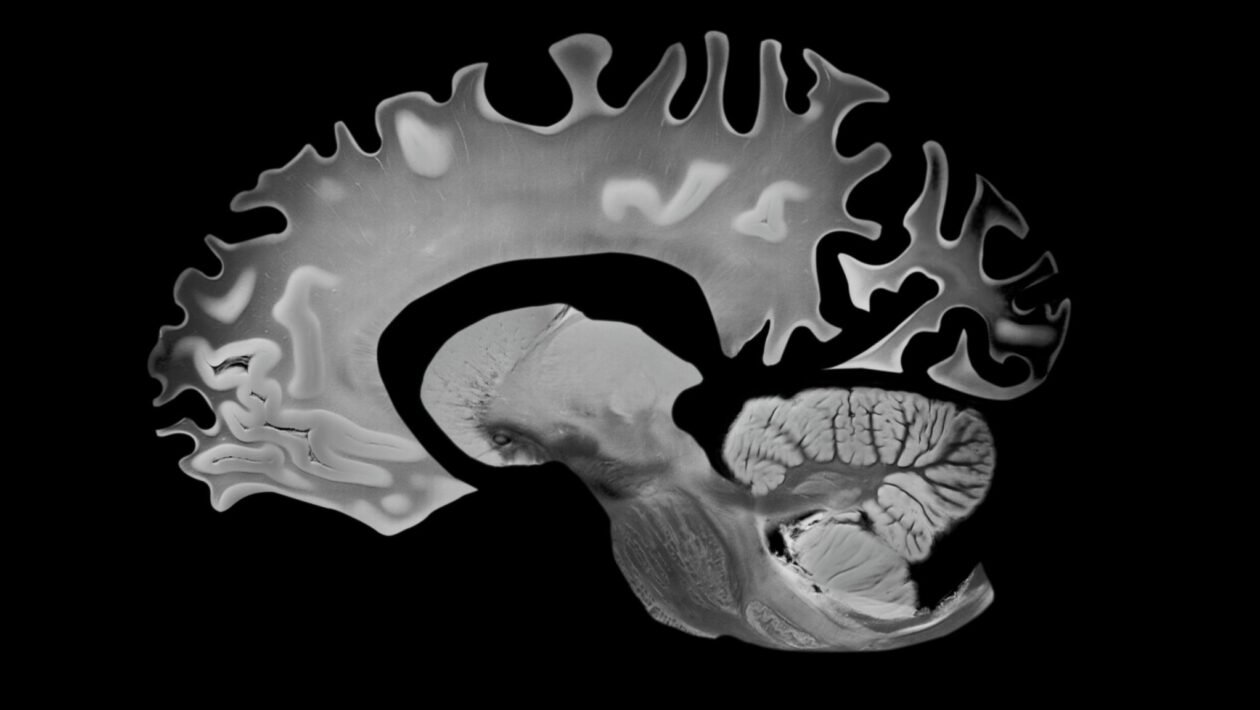

Corte lateral do cérebro evidenciando a atrofia associada ao Alzheimer. (Foto: VA via Canva)